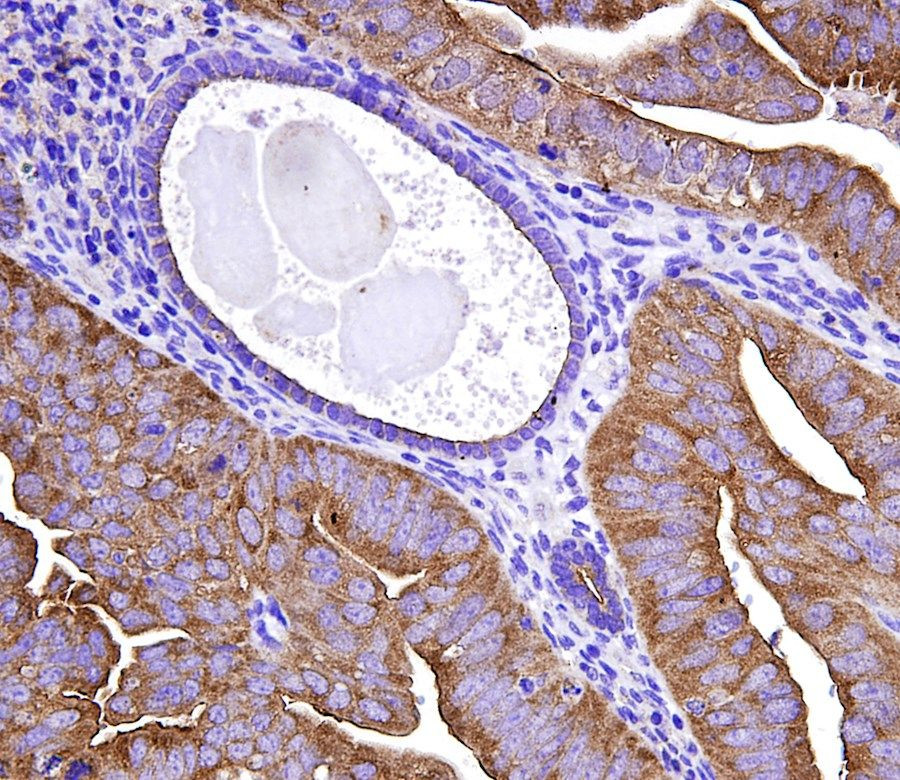

Utilizando líneas celulares, muestras de pacientes, modelos de ratones y técnicas computacionales, el equipo de Lin demostró que las abundantes proteínas mutantes en los cánceres IMS se deforman y son estructuralmente inestables.

A medida que las células tumorales cambian los recursos para ayudar a dar forma correcta a las proteínas mutadas, comienzan a fallar en la forma correcta de las proteínas normales, lo que finalmente hace que todas las proteínas dentro del tumor se vuelvan más inestables.

La abundancia de proteínas deformes requiere que las células tumorales utilicen una vía de degradación de proteínas que no suelen utilizar las células normales. MLN4924 puede bloquear esta vía, lo que resulta en toxicidad específicamente en las células cancerosas IMS.